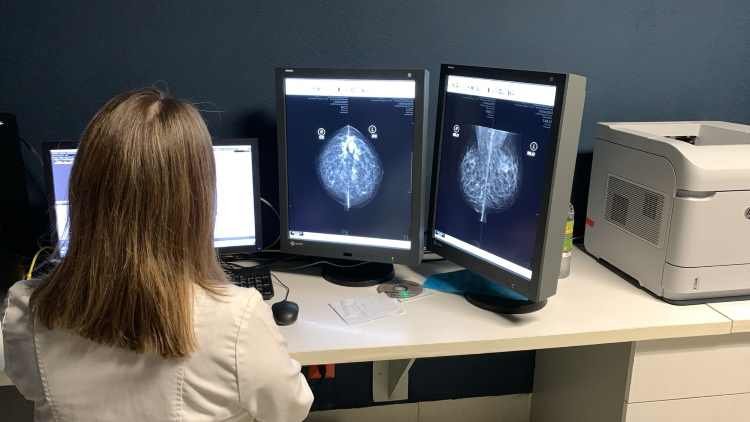

Señaló que la estrategia de detección, incluye la realización de mastografías de tamizaje en unidades especializadas en cáncer de mama en Victoria y Tampico, así como en hospitales generales y mediante unidades médicas móviles equipadas.

Durante el 2023, la dependencia estatal realizó más de 33 mil exámenes clínicos de mamas y se realizó tamizaje mediante mastografía a cerca de 13 mil mujeres; se realizaron ultrasonidos a más de mil pacientes que presentaban sospechas de anormalidades en sus mamas.

Para la aplicación de este programa es importante que las usuarias acudan a los centros de salud a realizarse tamizaje de exploración mamaria, si se detecta alguna anormalidad o hallazgo, se solicita ultrasonido mamario o mastografía para descartar y/o confirmar el diagnóstico.